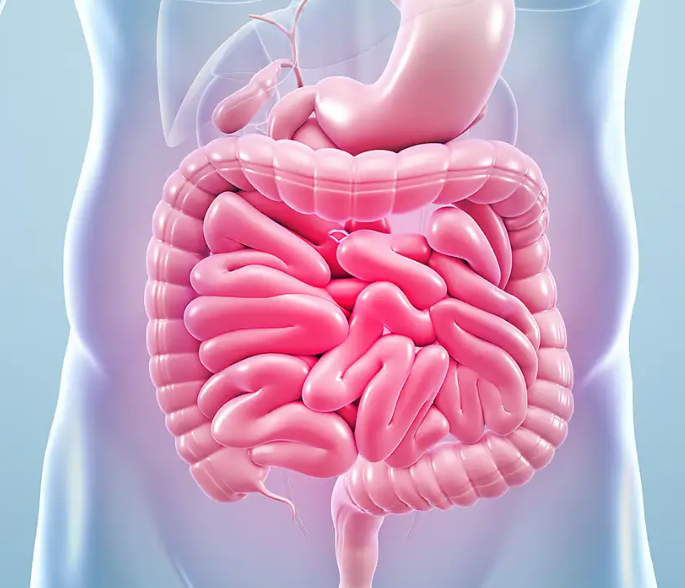

Leaky Gut Syndrome from a Clinical Perspective: Mechanisms, Diagnosis, and Evidence-Based Treatment Approaches Introduction to Leaky Gut Syndrome Leaky gut syndrome, characterized by impaired intestinal permeability, has gained attention in both scientific literature and clinical practice. This condition is associated with various gastrointestinal and systemic diseases, although its clinical significance remains a topic of debate. […]

Heal Your Gut, Heal Your Life: The Gundry Health Approach to Leaky Gut and Autoimmune Disease The gut is the foundation of overall health, influencing everything from immune function to mental well-being. When compromised, it can trigger a cascade of chronic illnesses, including autoimmune diseases. At Gundry Health, we understand that leaky gut syndrome (LGS) […]

10 Early Signs You May Be Suffering from Leaky Gut (And How to Heal It Naturally) Are you frequently struggling with digestive discomfort, fatigue, or unexplained skin issues? These could be early warning signs of a condition known as leaky gut, or increased intestinal permeability. Leaky gut occurs when the protective lining of the small […]

Why Your Gut Health Is Everything: A Deep Dive into the Microbiome, Mood, and Overall Wellness When Hippocrates famously declared that “all disease begins in the gut,” he was onto something profound—insights that modern science is now validating. In this blog post, we’re exploring just how pivotal gut health is for your entire body, from […]